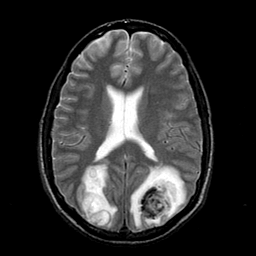

In this study, the dataset introduced in [8], which is publicly available111https://github.com/ChengBinJin/MRI-to-CT-DCNN-TensorFlow, is used for performance evaluation. It consists of 367 paired CT and MR images with the size of 512256. In the original dataset, it is noted that several CT images have stereotactic head frame that was used in Gamma Knife treatment. This head frame manually removed from the CT images. In addition, there exist various CT and MR slices that brings incredible difficulty in training the generator. Therefore, 100 images are selected from similar slices for each modality, in which 90 and 10 images are used for training and testing, respectively. Fig. 5 shows four examples of pre-processed samples.

Moreover, Figs. 6 and 7 show the synthesized MR and CT images along with the errors between the real and synthesized images by different methods, respectively. It can be seen that the synthesized images by DC-cycleGAN are more identical to the real ones as compared with other methods. This indicates that effectiveness of SSIM and CE along with dual contrast in synthesizing images. In addition, the error between the groundtruth and synthesized MR/CT images by DC-cycleGAN is relatively less as compared with other methods.